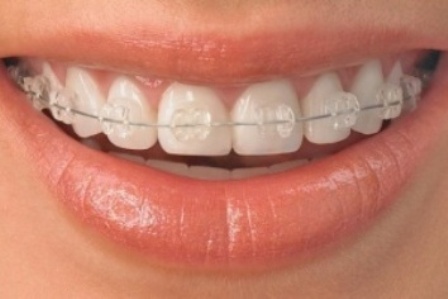

Fiksne proteze

Fiksne proteze, to jest fiksni ortodontski aparati, kako im sam naziv govori, ne skidaju se. Lepe se pomoću specijalnog lepka na zube i tu ostaju sve do kraja terapije...